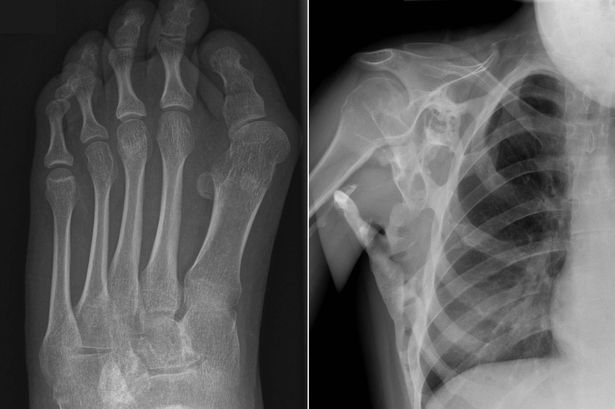

Durante seis anos ela batalha contra a condição chamada de “síndrome de pedra do homem ou fibrodisplasia ossificante progressiva (FOP). A condição – tão rara que afeta apenas 600 pessoas em todo o mundo – transforma os músculos, ligamentos e tendões em ossos sólidos.

Isso significa que um segundo esqueleto está crescendo lentamente em cima do original, fazendo com que seus membros gradualmente se solidifiquem para deixa-la como uma estátua.